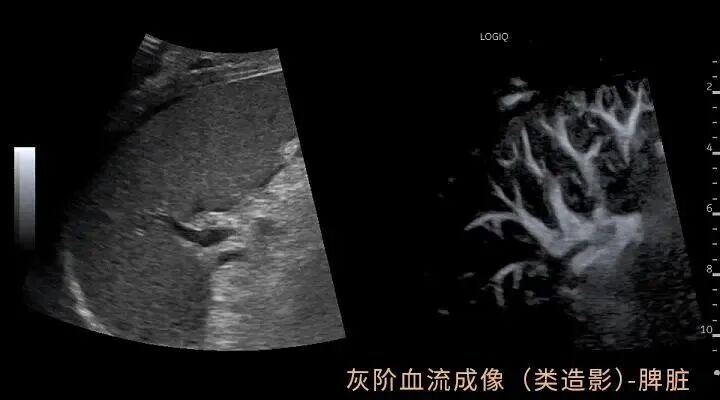

GE LOGIQ-Fortis Plus在甲状腺、乳腺、双下肢、颈部血管等检查项目方面有明显优势,对微血流的显示和弹性成像技术有全新的视野,图像更清晰细腻,血流显示立体逼真,能够实现二维条件下血流的“立体浮雕式”呈现,减少彩色血流闪烁,增强细微血管的可视化成像效果有利于临近交叉血管的边界识别。